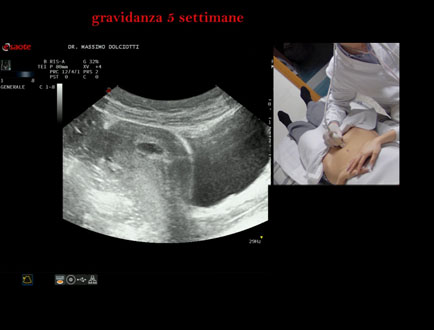

Data inserimento: 06/02/2026

Ecografia del: 28/01/2025

Strumento: Esaote MyLab Eight

Sonda: Convex Multifrequenza 1-8 MHz

Età Paziente: F 28 anni

Motivazione dell'esame: amenorrea.

Commento all'esame: le immagini ed il video documentano la camera gestazionale delle dimensioni di 11 mm e presenza di embrione delle dimensioni di 4,1 - 5,4 mm, con iniziale battito cardiaco.

Conclusioni: gravidanza alla quinta settimana di gestazione (pregnancy in the 5th week of gestation).

In collaborazione: Dr.ssa Marica Manfredi - Ancona, Dr. Ilir Qose - Ancona

Presentazione: Dr. Massimo Dolciotti - Ancona

Elaborazione digitale: Andrea Dini - Ancona